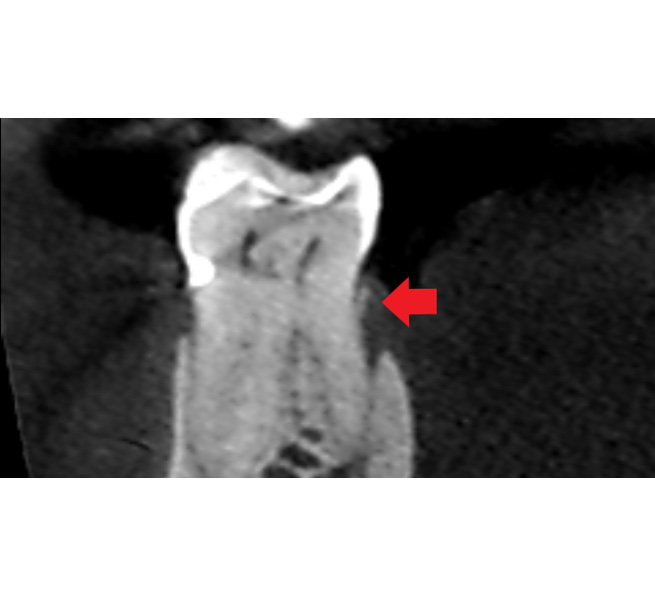

7歯茎が腫れる主な原因と治療法:Vol.4 歯根破折

歯根破折とは歯に過剰な力が加わって歯の根にヒビが入り、歯の根が割れた状態です。(用語集にリンク)このヒビにバイ菌が入り込み、歯茎の中に膿を持ち歯茎が腫れてきます。歯根破折は、歯ぎしりが関わっていることが多いです。

診断に関しては、歯根破折は肉眼や拡大鏡、レントゲン画像ではわかりづらく、CT画像と歯科用顕微鏡を組み合わせて診断するのが有効です。

一見、レントゲン画像ではわかりづらくても、CT画像だと特有の歯槽骨の吸収画像が見られ、確定ではありませんが歯根破折を予測する事ができます。そして、破折が予想されるところを顕微鏡を使用して強拡大で視認することにより、歯根破折を確定診断することができます。

もちろん、CTと顕微鏡があれば全て破折を発見できるというわけではありませんが、正しい診断ができる確率が上がります。